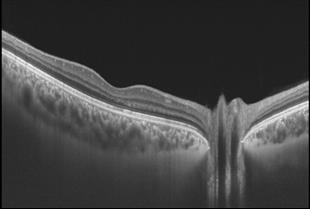

גלאוקומה, רשתית, זגוגית וOCT-. במרפאה קיים מכשור לבדיקת OCT ובדיקת OCTA.

עשרות מיליונים חולי סוכרת ברחבי העולם סובלים מבצקת זו, המהווה את הסיבה העיקרית לפגיעה בראיה בחולי הסוכרת. בניגוד לטיפול בבצקת זו בזריקות לתוך העין במשך שנים, הוכחנו בעזרת הדמיית OCT בתלת-מימד כי הגורם העיקרי לבצקת הינו מכני: משיכת המקולה ע"י קרומי זגוגית העין הסמוכים לרשתית והנמצאים במרחק של עד מספר מ"מ ממרכז המקולה (extrafoveal); ממצא זה לא מאובחן בבדיקת OCT סטנדרטית. כך נמצא שניתוח בודד להסרת משיכות הזגוגית (ניתוח "ויטרקטומי"), בעיניים "נאיביות", כלומר בעיניים שלא טופלו בזריקות בעבר, השיג ייבוש מלא וארוך טווח של המקולה ב-92-100% מהמחקרים.

ה) האבחון המוקדם ביותר של מחלת הגלאוקומה באמצעות בדיקת ההדמיה המאד-מדויקת, OCT (2010, 2003). גישה זו הפכה קבועה בעולם. לשם אבחון מדויק של גלאוקומה וגם באבחון בשינויים במשך תקופת המעקב יש צורך בבדיקת ראש עצב הראיה ב- OCT. הדיוק מונע טיפולים מוקדמים מיותרים, ולחילופין – מלמד על המועד הנדרש לתחילת הטיפול ועל צורך בשינוי בטיפול בעת המעקב.